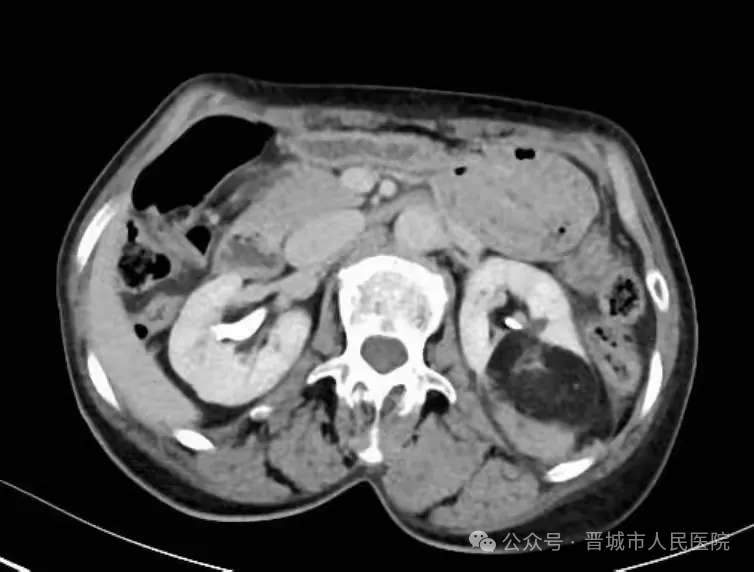

据了解,患者因体检发现左肾占位20余天入院,外院检查提示左肾肿物大小约45*55*98mm,接近十公分的肿瘤体积给治疗带来了极大挑战。更为棘手的是,患者年事已高,体质薄弱且营养状况欠佳,腹壁肌肉薄弱导致手术戳卡固定困难,传统腹腔镜手术操作空间受限、难度极高,而患者及家属保肾意愿十分强烈。